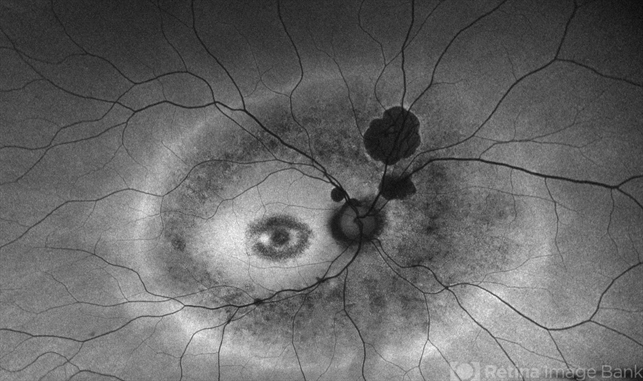

- inherited retinal disease, retinal dystrophy, retinitis pigmentosa, fundus autofluorescence (FAF), nyctalopia

- A 65-year-old male patient reports experiencing bilateral blind spots that have gradually intensified over time. Genetic testing was unrevealing. The fundus autofluorescence image shows a hypoautofluorescent ring in the posterior pole, especially nasal to the nerve and along arcades.